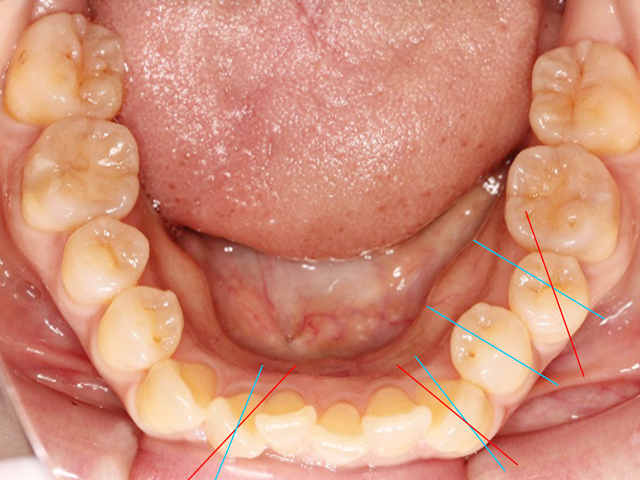

下顎の画像です。上と同じく前歯のスペースが不足しています。

右下の中切歯は「近心捻転(きんしんねんてん)」、左下の側切歯は「舌側転位」と呼ばれる状態になっています。

こちらの画像は別の患者さんのものです。明らかに捻転とわかる歯牙に線を入れました。青線は本来向いているべき方向で、赤線は捻転の方向を入れました。

左下第1小臼歯が正しい状態とすると、手前の犬歯は遠心捻転、1つ後ろの第2小臼歯は近心捻転の状態です。